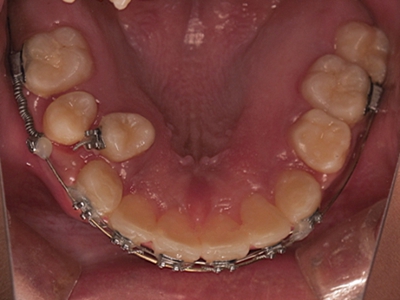

阻生牙是指由于邻牙、骨或软组织的阻碍而只能部分萌出或完全不能萌出,且以后也不能萌出的牙。引起牙阻生的成因,主要是由于颌骨缺乏足够的空间容纳全部恒牙。常见的阻生牙为下颌第三磨牙、上颌第三磨牙及上颌尖牙。

阻生牙可反复引起冠周炎,或引起邻牙牙根吸收和破坏,位置不正,不能完全萌出,好发部位是上、下颌第三磨牙。

发育正常的牙齿同时正畸治疗又不需要进行拔牙矫治,通常需要对阻生牙进行牵引治疗,引导进入牙弓,而对于发育异常的阻生牙加之正畸治疗需要进行拔牙矫治,通常可以考虑将阻生牙拔除,而避免再拔发育正常的前磨牙,即降低了正畸治疗的难度及不确定性,又保留了相对正常的牙齿。